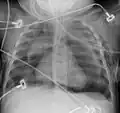

El diagnóstico puede confirmarse mediante una radiografía de tórax en la que aparezca un contorno radiolúcido alrededor del corazón y el mediastino o mediante un TAC de tórax.

-

Neumomediastino y neumotórax derecho tras fractura de la primera costilla en accidente de bicicleta de montaña. -

Neumomediastino con el signo del ala de ángel.[18] -

Neumomediastino observado en ecografía.[19]